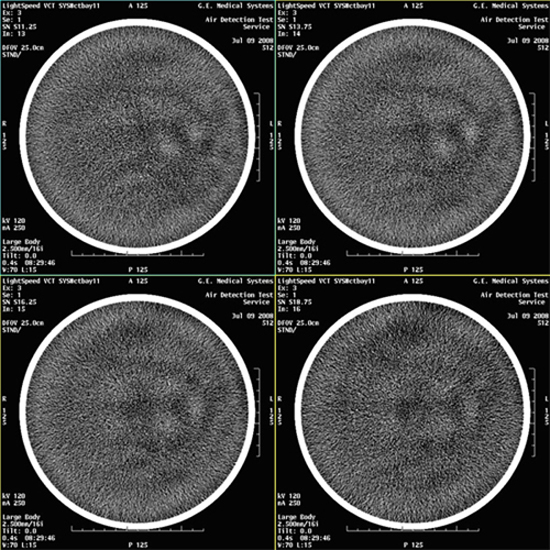

- Select VIEWER and review all images for

blotchy artifacts. (See Figure 1, Figure 2, and Figure 3). If an artifact is encountered, perform Tube Oil

Cooling System Air Removal.note:

If air artifact exists, the air activity may be more significant in Images 13 through 16, 29 through 32, 45 through 48, and 61 through 64.

Figure 3. Images with Artifacts